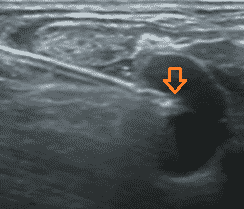

El acceso a la vena yugular se realiza bajo control ecográfico mediante abordaje lateral con una curva más fisiológica del catéter.

La sonda es ortogonal a la vena pero la aguja es paralela al eje principal de la sonda, como visto anteriormente.

Esto hace que sea mucho más fácil seguir la aguja en casi todo su recorrido:

Nunca se debe pinchar la pared posterior de la vena, es decir nunca se debe hacer transfixión. Esto evita la punción arterial de la arteria carótida